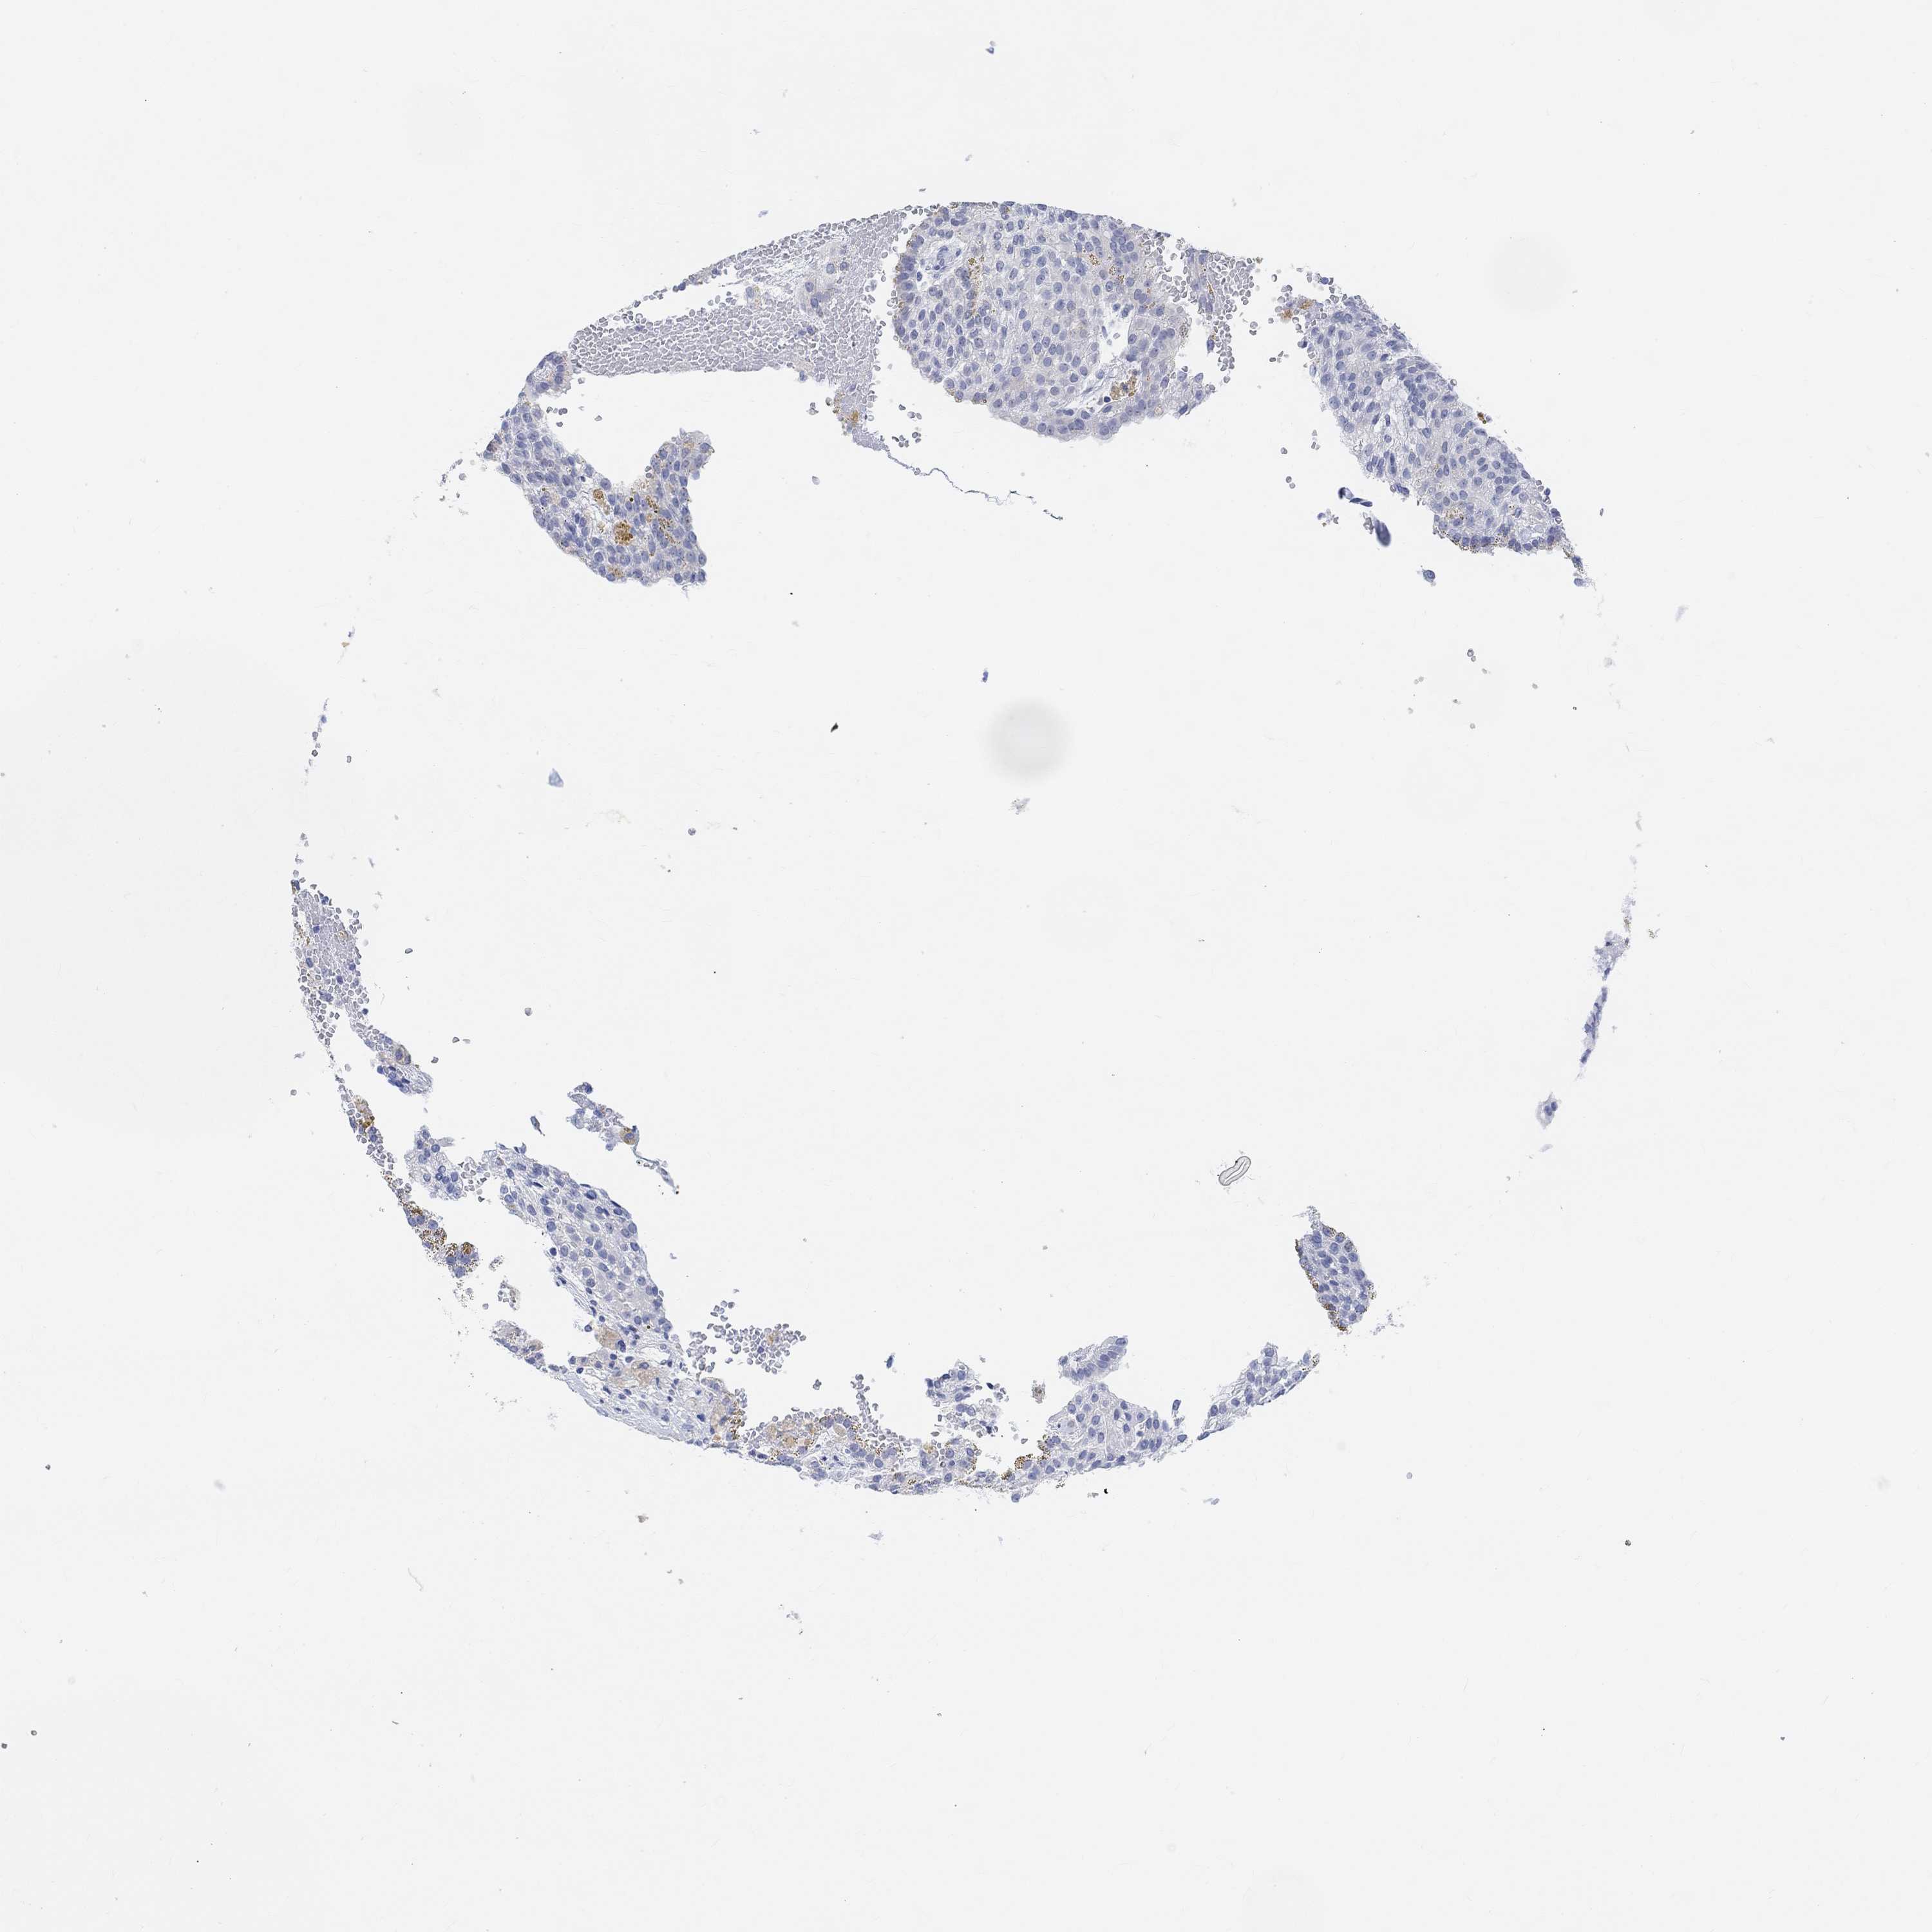

CANCER RENAL CANCER Show tissue menu

KICH TCGA KIRC TCGA KIRC VALIDATION KIRP TCGA PROTEIN RCC CPTAC PROTEIN EXPRESSION